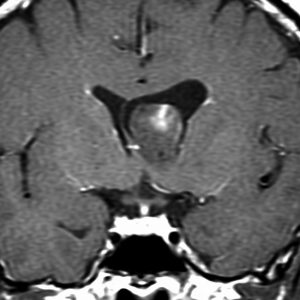

片側性水頭症

左尾状核から発生したものです。モンロー孔を閉塞して,片側性水頭症となっています。腫瘍がトリュフみたいにゴツゴツしているのも特徴です。

下のガドリニウム増強T1では,部分的に増強されます。

もちろん無症状ですが,年齢が若かったので全摘出しました。